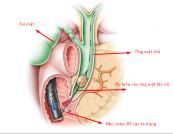

Nội soi đường mật ngược dòng (ERCP) kiểm tra các ống dẫn lưu gan, túi mật và tuyến tụy. Hình ảnh nội soi và hình ảnh X-quang được sử dụng. Để hiểu rõ hơn về thủ thuật này, mời các bạn tham khảo bài viết dưới đây!